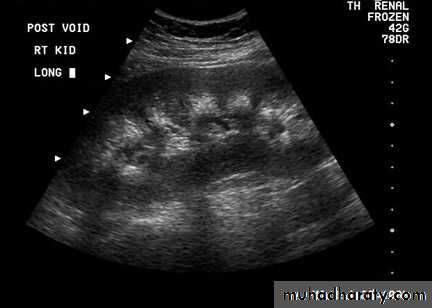

Localization of the adenoma

UltrasoundNeck MRI

99m Tc-sestamibi scintigraphy